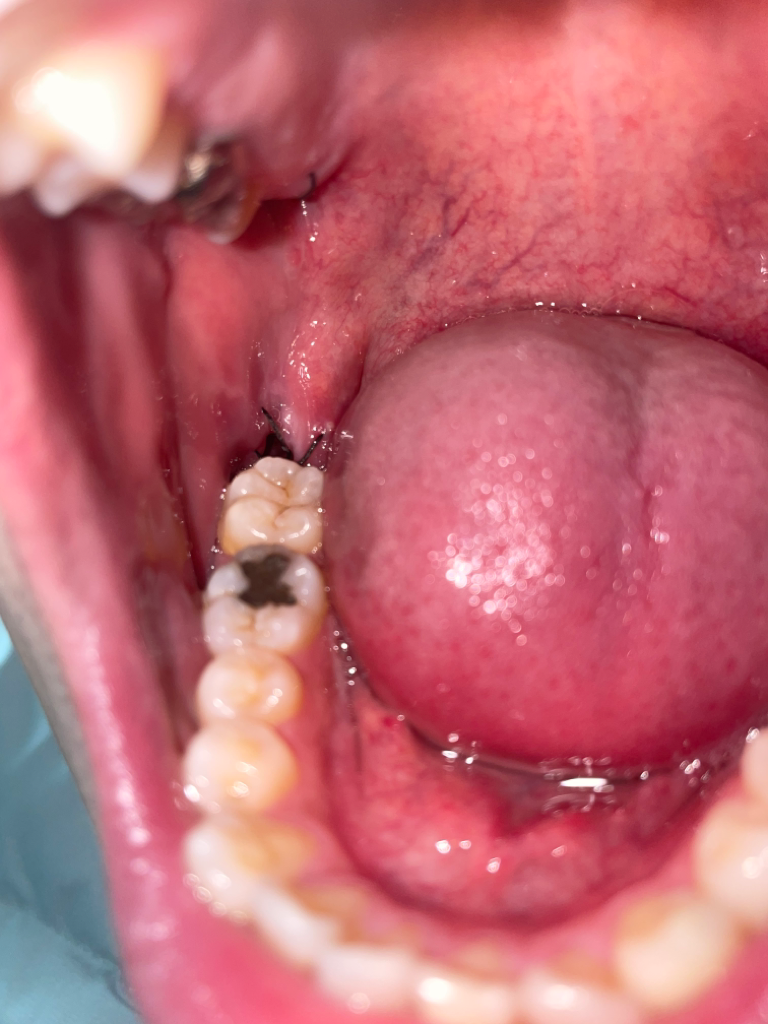

발치부위가 앞 어금니에 가려 잘 보이지는 않네요. 그런데 보통 일주일정도 지나면 진통제를 먹을만큼의 통증은 아닐텐데 아직도 많이 아프시다면 염증이 생겼을 가능성이 있어요. 실밥은 보통 발치 후 7~10일에 푸는데 오래 놔두면 오히려 이물질이 붙어 더 안좋을 수 있어요. 치과에 가셔서 어떤 문제인건지 알아보시는게 좋을 것 같아요. 염증 생긴거라면 항생제도 같이 처방해 드릴꺼예요.

매복사랑니발치후 보통 통증이 5일정도 지속될 수 있습니다.

그 이상 심한통증이 지속된다면 건치와의 가능성이 있습니다.

우선 실밥제거시에 치과에 통증에 대해 문의해보시기 바랍니다 감사합니다.

통증이 극심하다면 염증의 가능성이 있습니다. 구멍은 메꿔지는데 한달이상 걸리며 통증은 점차 줄어드는것이 맞습니다

사랑니 발치후에 하루이틀정도면 어느정도 통증은 사라집니다. 일주일이 지낫는데도 아프디사면 드라이소켓일 가능성이 잇으니 치과에 가셔서 소독을 한번받으시는게 좋을것같습니다.